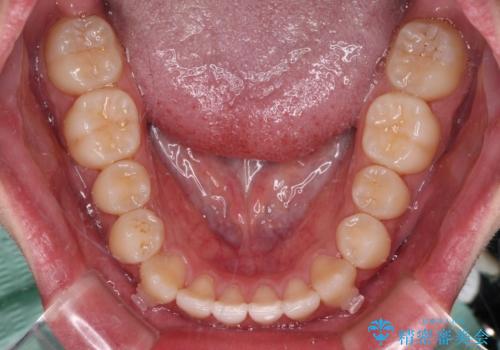

受け口傾向の骨格であり、前歯はクロスバイトまたは切端咬合となっており、叢生は警備であったため、下顎を中心に歯列全体の後方移動を行い、IPR(歯と歯の間を削る)によってデコボコが解消するように設計し、インビザラインにより治療を行うこととしました。

受け口傾向のインビザライン矯正は比較的治療を行いやすいため、きれいに仕上げることができました。舌の突出癖が顕著であったため、改善のためのトレーニングをしっかりと行っていただきました。